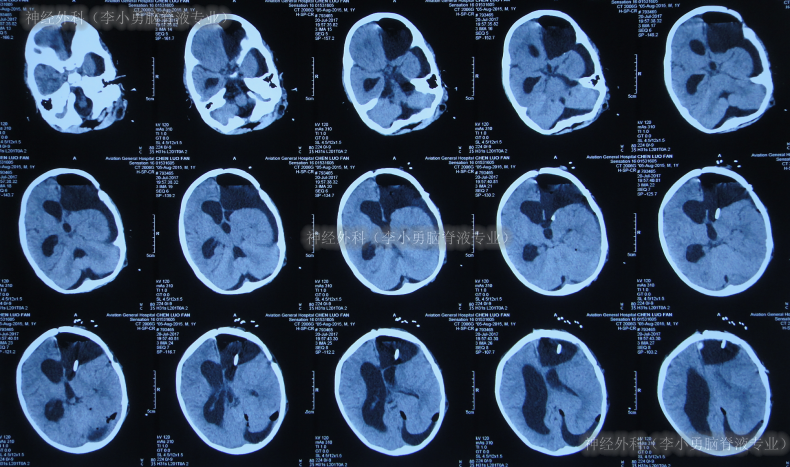

患儿于出生后10月龄即2016年6月1日,患儿意外摔伤头部,在当地的福建省福州市某医院,查头颅CT(图-1)后给予保守治疗后出院观察。

图-1:2016年6月1日头颅CT